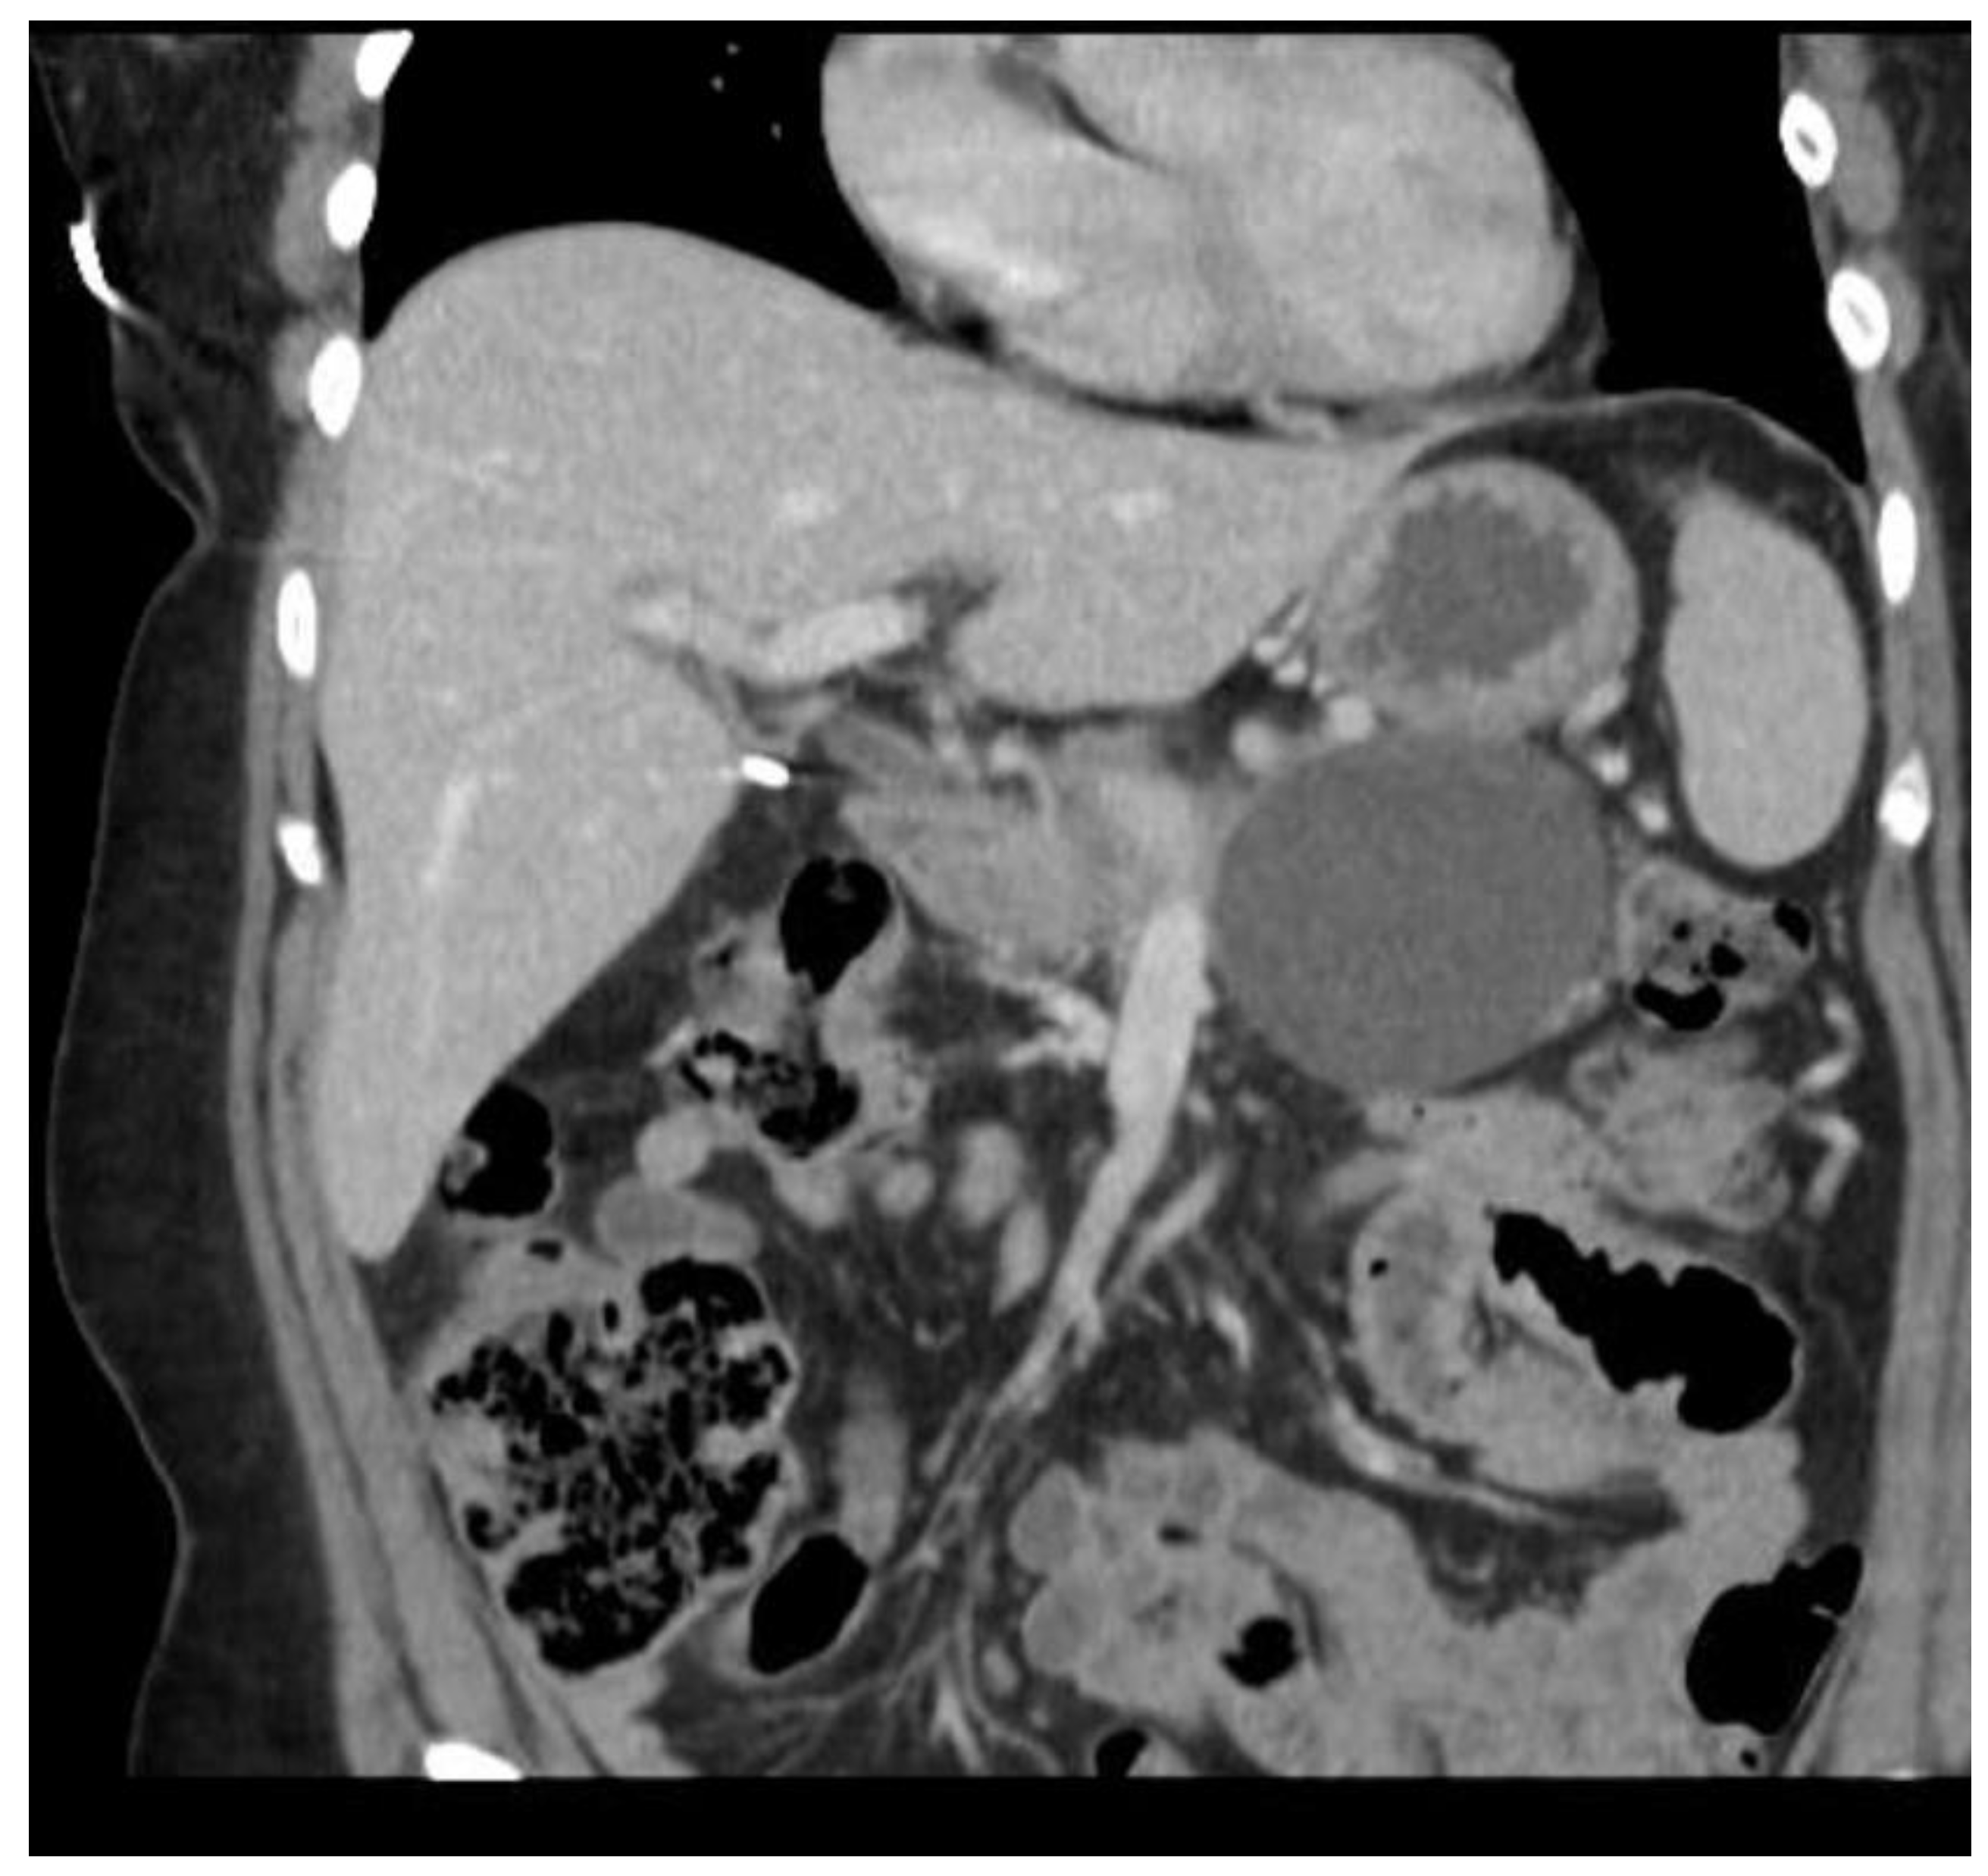

3.2. Severity of Pancreatitis

The prediction of severity is made upon the admission of the patient, but the actual degree of severity is determined once sufficient time has elapsed in order to make a better assessment of acute pancreatitis. The most widely accepted classification of severity is the Revised Atlanta Classification (RAC) [4], which classifies pancreatitis as follows: (1) mild acute pancreatitis with no local inflammation or organ failure, (2) moderately severe acute pancreatitis with transient organ failure (<48 h) or local complications, and (3) severe acute pancreatitis with persistent organ failure (>48 h). In total, 65–70% of patients with acute pancreatitis have an uncomplicated course in which the symptoms resolve within a few days [4,43]. A total of 20–25% of patients develop moderate acute pancreatitis with local pancreatic injury fluid collection or necrosis, leading to prolonged hospitalization. This progression is displayed in Figure 4, Figure 5 and Figure 6. About 10% of patients develop severe acute pancreatitis accompanied by severe pain, a nutritional deficit, and a hospital stay > 4 weeks. These patients require highly intensive critical care with interventions (as indicated) [24].

Figure 5. Acute interstitial pancreatitis with developing peripancreatic fluid collection.